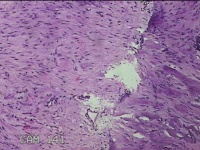

左耳赘生物

性别

女

年龄

23岁

临床诊断

纤维瘤?

一般病史

左耳皮肤起新生物2年。

标本名称

大体所见

灰白暗红色组织1.8x1.5x0.7cm,表面光滑,切面灰白粉红色,质软。